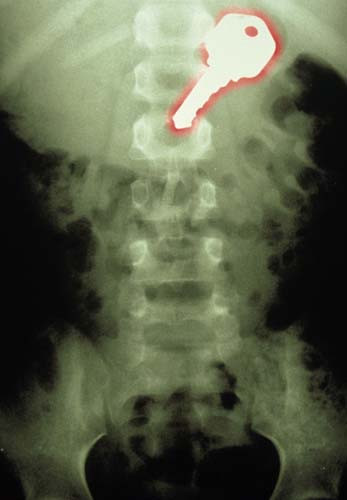

7 yaşında bir çocuk tarafından yutulmuş anahtar...